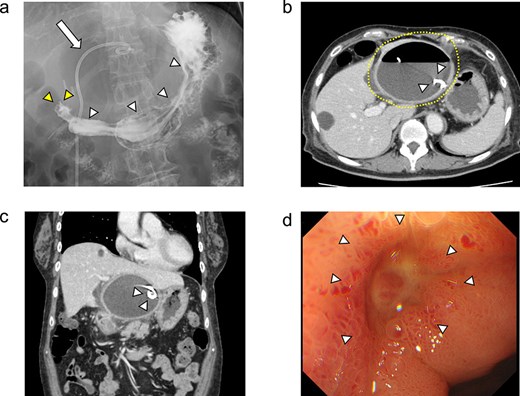

She was discharged home uneventfully on the 10th day after the surgery. CT has identified no evidence of recurrence 6 months postsurgery (Fig. 4).

Plain CT image 6 months after the patient’s surgery. There was no evidence of hepatic cyst recurrence.